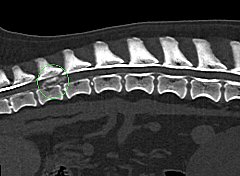

CT CT

本院では、4列マルチスライスヘリカルCT装置(TOSHIBA Asteion4)を導入しました。

1回転で4断面の画像を取得することができ,0.75秒の高速フルスキャンを可能とすることで,肺野領域30cmの範囲を最速6秒以下でスキャン可能です。

従来の1列のCTより短時間で、被爆量の少ない、正確な検査が可能です。

• 椎間板ヘルニア

骨盤骨折 椎間板ヘルニア